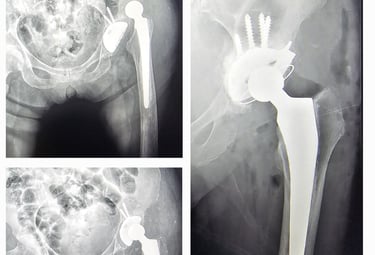

Cirugía de revisión de prótesis de cadera/rodilla: es una operación que se realiza cuando una prótesis ya no funciona adecuadamente, ya sea por aflojamiento, desgaste, infección o dolor persistente. En este procedimiento se retira la prótesis dañada y se coloca una nueva, con el objetivo de devolver estabilidad, movilidad y mejorar la calidad de vida del paciente.

Displasia del desarrollo de cadera: es una alteración en la formación de la articulación de la cadera que está presente desde el nacimiento. Puede provocar que la cabeza del fémur no encaje bien en el acetábulo (la cavidad de la pelvis), lo que con el tiempo ocasiona dolor, cojera y desgaste temprano de la articulación. Su detección y tratamiento oportuno permiten prevenir complicaciones y preservar la función de la cadera.

Secuelas de displasia de cadera

Prótesis de cadera y rodilla